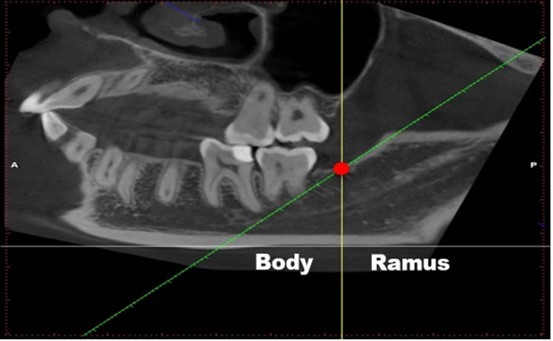

The second reading process was somewhat different: the researchers adjusted the sagittal images to make the lower edge of the mandible parallel to ground, then: (1) a horizontal line was made parallel to the lower edge of the mandible (Figure 1, grey line); (2) a tangent line was made along with the front edge of the mandibular ramus (Figure 1, green line), which intersects with the upper edge of the mandibular body (Figure 1, red circle); (3) a line across the intersection was made vertical to the line in (1) (Figure 1, yellow line). We defined the following: the bifurcation that appears in front of this vertical line (yellow line) is classified into mandibular body area, whereas the bifurcation that appears behind it is the mandibular ramus area (Figure 1). The classification of each type depends on the starting point of the bifurcation. Details are provided in Table 1.

Figure 1.Image-reading position. (1) a horizontal line was made parallel to the lower edge of the mandible (grey line); (2) a tangent line of the front edge of the mandibular ramus (green line), which intersects with the upper edge of the mandibular body (Fig. 1, red circle); (3) a line across the intersection was made vertical to the line in (1) (Fig. 1, yellow line). We defined the following: the bifurcation that appears in front of this vertical line (yellow line) is classified into mandibular body area, whereas the bifurcation that appears behind it is the mandibular ramus area (Fig. 1).